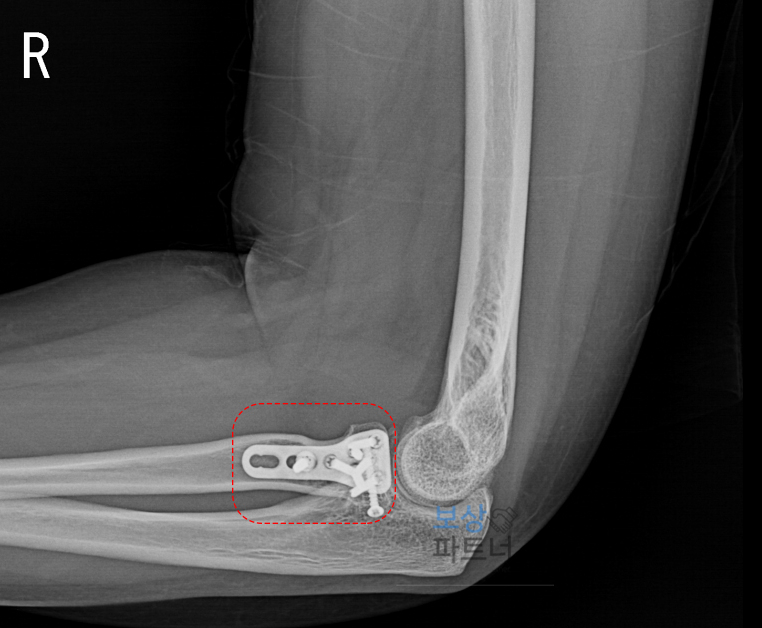

결국 의뢰인께서는 뼛조각을 직접 맞춘 뒤, 금속판과 나사로 고정하는 수술을 받으셨습니다. X-ray 상 팔꿈치 관절 부위에 금속판과 나사못이 삽입된 모습이 확인되는데요. 관절 내 골절이었기 때문에 안정적인 고정을 위해 내 고정물이 사용되었습니다.

후유장해보험금을 신청하기 위해선 '후유장해진단서'가 필요합니다. 의뢰인께서는 6개월이 지난 후 가장 먼저 수술을 집도한 주치의를 찾아가 후유장해진단서 발급을 요청했습니다. 하지만 주치의는 X-ray 상 뼈가 잘 붙었다며 이 정도는 후유장해에 해당하지 않는다며 발급을 거부했죠.